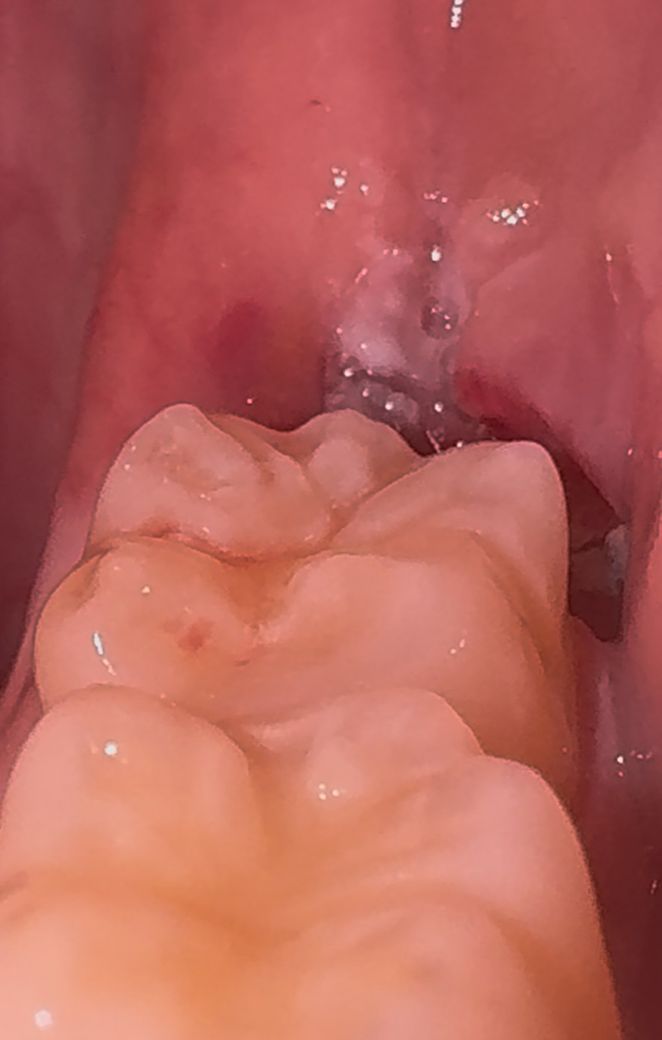

사랑니 발치 후 흰색 덩어리같은게 껴있어요

금요일에 매복사랑니 발치한 자리인데 저 이상한 하얀색 덩어리같은 것들이 껴있는데 뭔가요? 치과에 다시 가봐야하는건지 궁금하네요

잇몸이 치유되면 하얀색 막이 생기는 것이 정상적인 반응이니 걱정하지 않으셔도 되겠습니다.

그냥두어도 됩니다. 발치한 부위 가장자리에 희게 딱지 앉은 것으로 보면 됩니다. 잇몸 가장자리는 희게 딱지 않습니다.저절로 없어집니다.

사랑니 발치를 하고나서 잇몸이 치유되면서 생기는 자연스러운 현상이니 너무 걱정하지 않으셔도 될것같습니다.

사랑니를 발치하게 되면 해당 부위에 가피가 형성되거나 이물질이 들어갈 수 있습니다. 크게 문제를 발생시키지 않기 때문에 굳이 억지로 제거하려고 할 필요는 없습니다. 억지로 제거하려고 하다. 상처가 생기게 되면 치유가 늦어질 수 있기 때문입니다

치과에 다시 갈 필요가 있는 정도의 문제점은 아닙니다 발치 부위 치유 과정에서 나타나는 염증,육아조직으로 보입니다